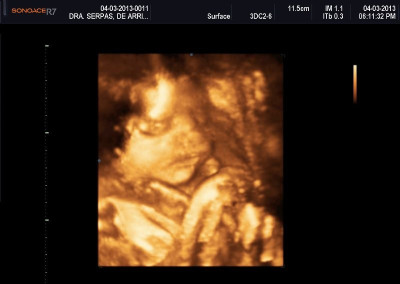

Varias ultrasonografías en 2D y 3D

Envíado por Dr. Nelson Menjívar Sarco